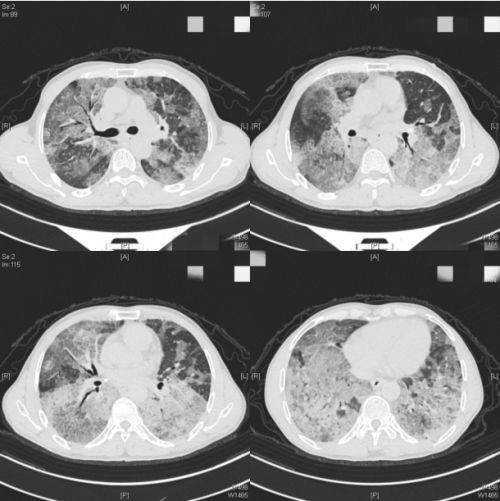

呼吸与危重症医学科求诊。入院时,医生发现常先生血氧饱和度仅为60%(正常人是95%以上),胸部CT显示双肺弥漫性病变,血气分析提示严重I型呼吸衰竭,查体双肺可闻啰音(弥漫性肺间质纤维化患者吸气后期出现的声音),杵状指(部分晚期患者可出现此症状)。科室迅速完善支气管镜活检,诊断其为肺泡蛋白沉积症,俗称“牛奶肺”。

患者入院时肺部广泛弥漫性病变

“肺泡蛋白沉积症是以肺泡表面活性物质灶肺泡巨噬细胞和肺泡腔内异常沉积导致的以呼吸困难为主的弥漫性肺疾病,是罕见的呼吸系统疾病。”据呼吸与危重症医学科主任、主任医师杨红忠介绍,肺泡蛋白沉积症可分为原发性、继发性和先天性,原发性是目前发病率最高的类型,但也需警惕继发于血液系统疾病、恶性肿瘤等所致的继发性肺泡蛋白沉积症,主要症状为胸闷、呼吸困难、咳嗽、咳痰、咯血等,临床症状及体征轻,影像学表现重,肺部CT表现为“铺路石”“地图样”改变。